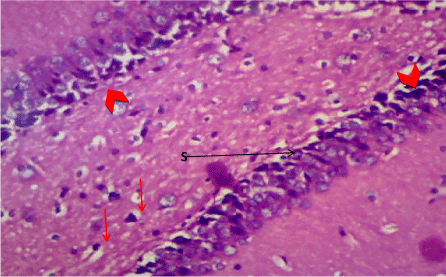

Haematoxylin & Eosin: The Normal control group (Figure 6) shows normal neuronal cells with distinctive cell layers, Diabetic control group (figure 7) shows increased pericellular spaces and chromatolysis signifying neuronal cell damage or neurodegeneration, Z. officinale treated diabetic group (Day 14) (Figure 8) shows restoration of neuronal cells with distinctive characteristic cell layers, Z. officinale treated diabetic group (Day 21) (Figure 9) shows restoration of neuronal cells with neuronal cell and layers and Metformin treated diabetic group (Figure 10) shows partial restoration of neuronal cells cell layers [7].

Figure 10. Photomicrograph of the hippocampus of Group E, more pericellular spaces indicating cell damage (S). (H&E) X100

Hippocampus: The hippocampus forms part of the limbic system and functions majorly in long-term memory and spatial navigation. Damage in any cell in the hippocampus can cause gross effects on the learning process of the individual. Astrocytes are most numerous glial cells in the brain and they help in the filling of spaces forming glial scars caused by neuronal damage and also help to repair the damaged cells that cannot be regenerated and a reduction in the number of these glial cells that help keep neuronal cells connected will cause a deficit in cell to cell connection. Figure 16 shows the normal hippocampus showing the different cell layers with no neuronal injury which is in support with the biochemical findings on free radicals and antioxidants. Figure 7 (Diabetic control) as compared to figure 6 (normal control) shows neuronal injury which was prominent throughout the granular layer which is in support with the biochemical analysis done on free radicals and antioxidants which shows elevated levels of free radicals and reduced levels of antioxidants proving low defence against free radicals which caused an increase in neurodegeneration and this was evident in the behavioural study. Diabetic control (Figure 11) shows degenerated pyramidal cells with short and disconnected processes and also has very few astrocytes with pericidal spaces. Figure 12 and figure 13 (Diabetes+ Z. officinale 14 and day 21) showed well preserved pyramidal cells in both groups. Figure 13 shows preserved neuronal cells as compared to that of figure 11, the astrocytes seen in figure 12 were numerous compared to that of the other groups which confirms the neuroprotective effect of Z. Officinale on brain cell and this finding is in agreement with, which observed that the administration of Z. officinale to diabetic rats increased astroglial response to injury which improved neurogenesis [9].